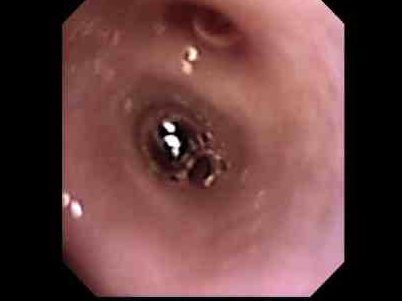

本症例は、臍ヘルニア整復時に飼い主様のご希望で鼻腔内の観察を行ないました。 今回使用したのは、細径タイプ(口径 2.8mm)です。

内視鏡を口からいれ、咽頭部の方から鼻腔内を観察しました。

左が咽頭部の写真です。粘膜面も綺麗で異常はありません。

右が鼻腔内の写真です。写真の左側に発赤、右側には粘液性の過剰分泌物が確認されました。